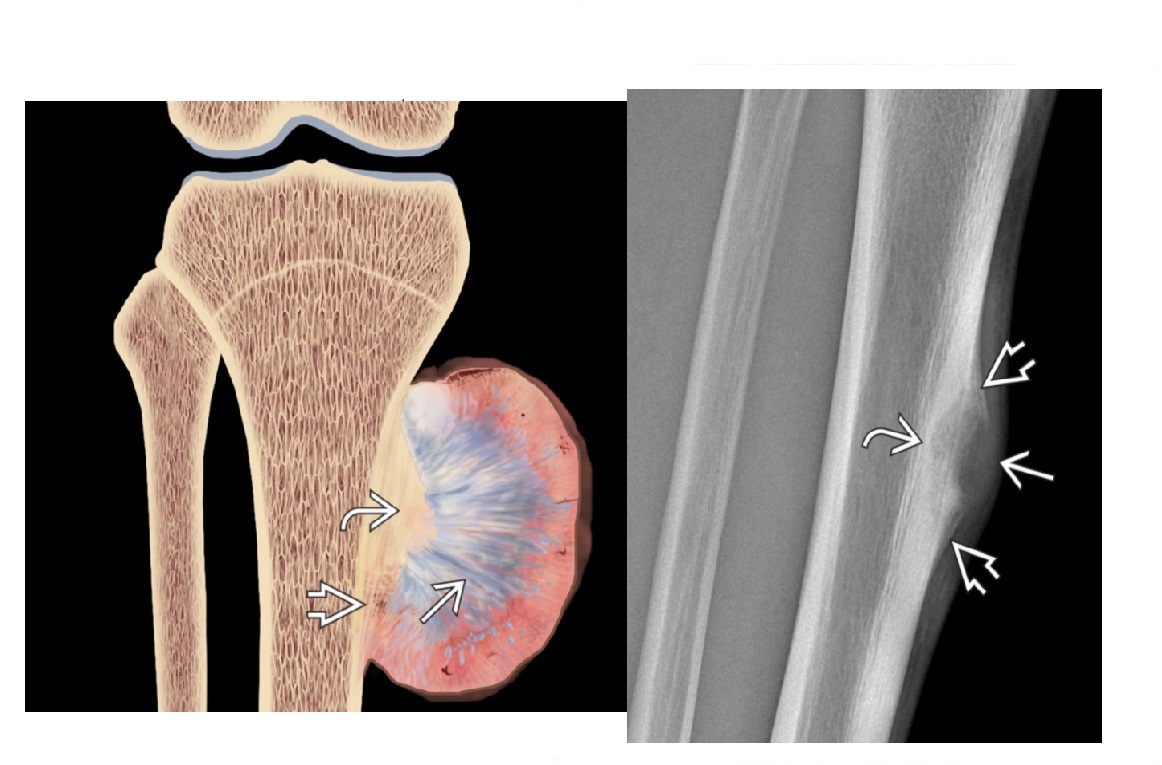

osteosarcoma

Femur (40%) and proximal tibia commonest sites (15%)

**Aggressive periosteal reaction **

- Sunburst

- Codman triangle

- Lamellated (onion skin)

**High grade = Met to the lung

**

Reverse zoning phenomenon - dense mature matrix in the centre, less peripherally